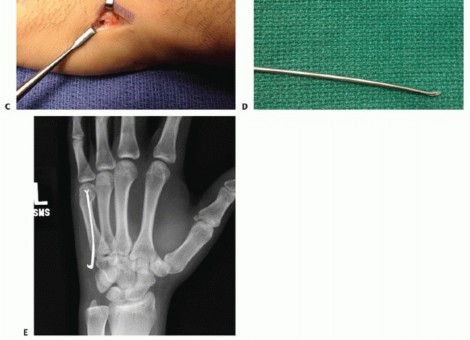

ANTEGRADE BOUQUET PINNING

This technique requires a rotationally stable fracture that can be reduced through closed means (TECH FIG 2A).An incision is made at the base of the metacarpal. Careful dissection is carried through the soft tissues protecting the cutaneous nerve branches. The extensor tendons are retracted and the metaphysis of the base of the metacarpal is exposed.In the case of a fifth metacarpal, it is easier to make this approach straight ulnar as opposed to dorsal (TECH FIG 2B).A unicortical 2.7- or 3.5-mm tunnel is made with a drill. This tunnel is created angled in a proximal to distal direction (TECH FIG 2C).Commercially available sets include an awl that helps in establishing the tunnel through which the definitive fixation is placed.Two or three prebent wires (TECH FIG 2D) are then advanced through the tunnel, across the fracture, and lodged into the metacarpal head subchondral bone (TECH FIG 2E).Great care must be exercised advancing the wires to prevent them from penetrating through the opposite cortex.The wires can be advanced with a needle holder or a pin holder using some gentle oscillation.The hand is initially immobilized in a forearm-based splint with the MP joint in 70 to 90 degrees of flexion while allowing some motion of the IP joints.If stable fixation is accomplished early, MP joint motion is initiated. The affected finger can be buddy taped to the adjacent finger to avoid rotational forces across the fracture.The wires may be removed after 4 weeks or, if cut at the level of the bone, they may be left in place indefinitely.

TECH FIG 2 • A. Angled metacarpal neck fracture. B. Incision at the ulnar base of the fifth metacarpal, exposing the insertion of the extensor carpi ulnaris (ECU) on the base of the metacarpal. Incision located on ulnar aspect of metacarpal to minimize irritation of the extensor tendons. C. Unicortical tunnel at the base of the metacarpal. D. Sample of prebent pin. Tip is angled to facilitate passage through the shaft. E. In metacarpal neck fractures or those at risk of shortening, it is important to bring the pins to the subchondral bone of the metacarpal head but not violate the head.